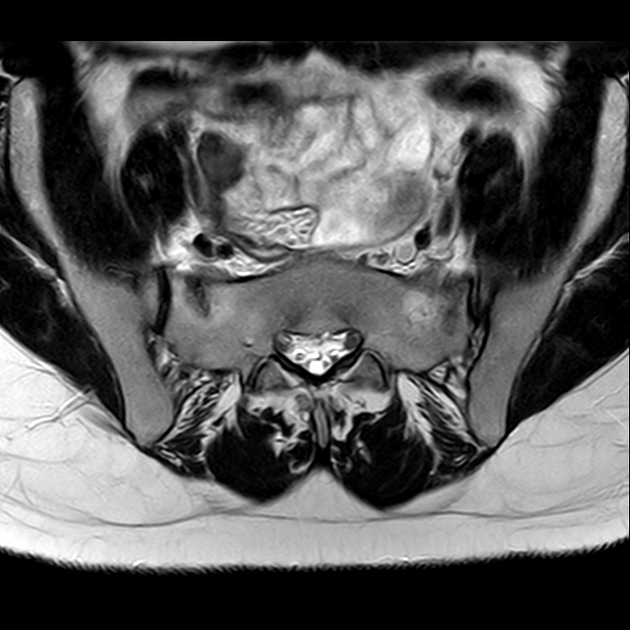

磁共振检查:

STIR

6、磁共振上可以发现骨折线周边明显的骨髓水肿,增强扫描明显强化

磁共振影像表现